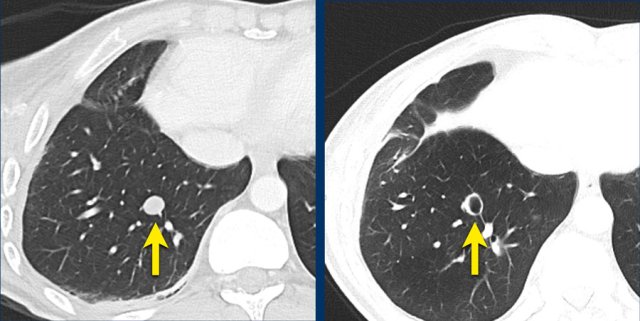

The images are of a patient with a primary lung tumour.

At baseline, the longest diameter is well above 10 mm, therefore this was assigned as a target lesion.

During follow-up the long-axis diameter dropped below 10 mm, which is the lower limit for considering a lesion as target lesion.

However, since this is a follow-up measurement, the target lesion still counts up to the sum of the diameters (SLD) and a default value of 5mm was assigned.